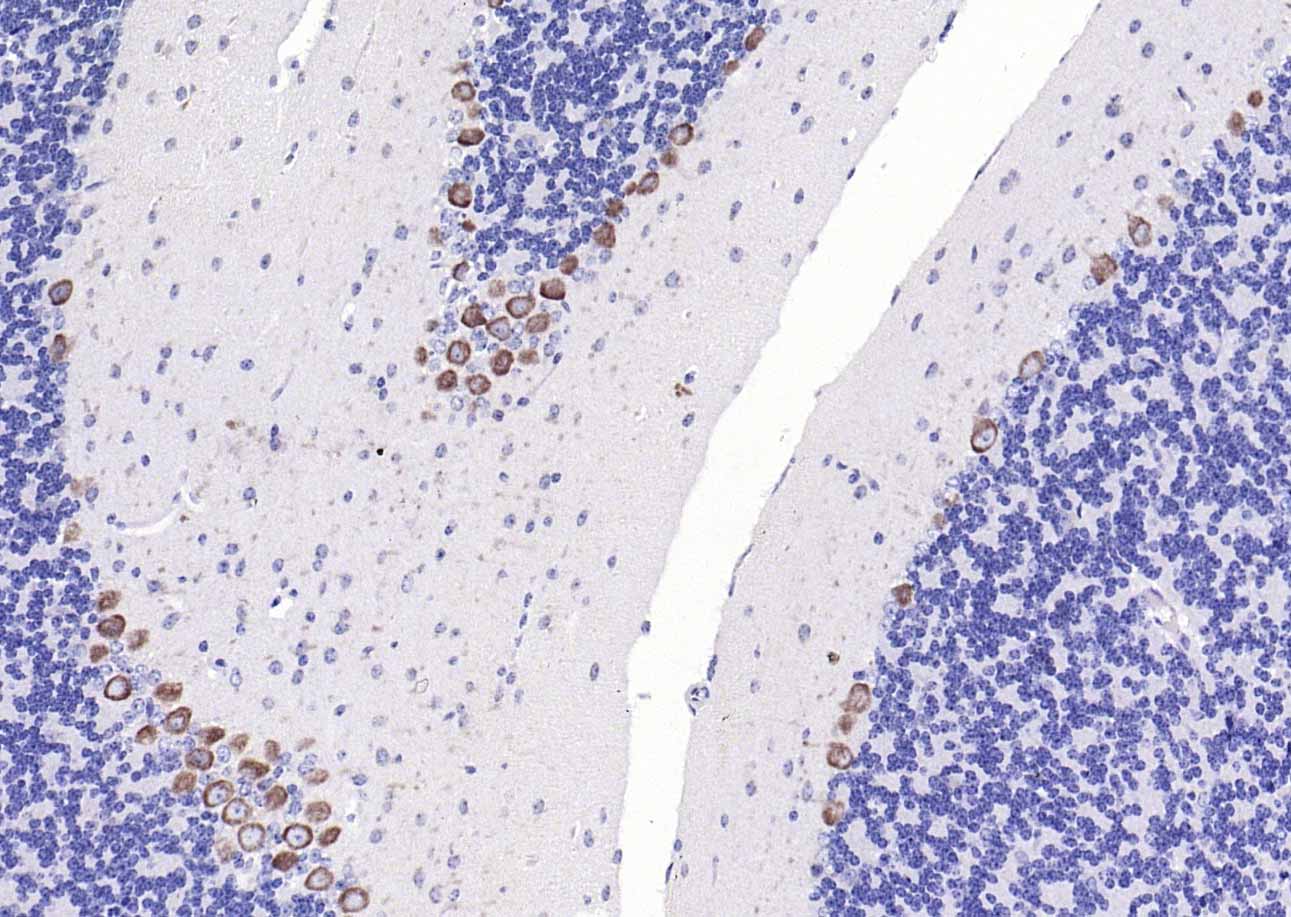

Paraformaldehyde-fixed, paraffin embedded (rat brain); Antigen retrieval by boiling in sodium citrate buffer (pH6.0) for 15min; Block endogenous peroxidase by 3% hydrogen peroxide for 20 minutes; Blocking buffer (normal goat serum) at 37°C for 30min; Antibody incubation with (CACNA1G + CACNA1H) Polyclonal Antibody, Unconjugated (bs-11984R) at 1:200 overnight at 4°C, followed by operating according to SP Kit(Rabbit) (sp-0023) instructionsand DAB staining.

Paraformaldehyde-fixed, paraffin embedded (mouse brain); Antigen retrieval by boiling in sodium citrate buffer (pH6.0) for 15min; Block endogenous peroxidase by 3% hydrogen peroxide for 20 minutes; Blocking buffer (normal goat serum) at 37°C for 30min; Antibody incubation with (CACNA1G + CACNA1H) Polyclonal Antibody, Unconjugated (bs-11984R) at 1:200 overnight at 4°C, followed by operating according to SP Kit(Rabbit) (sp-0023) instructionsand DAB staining.